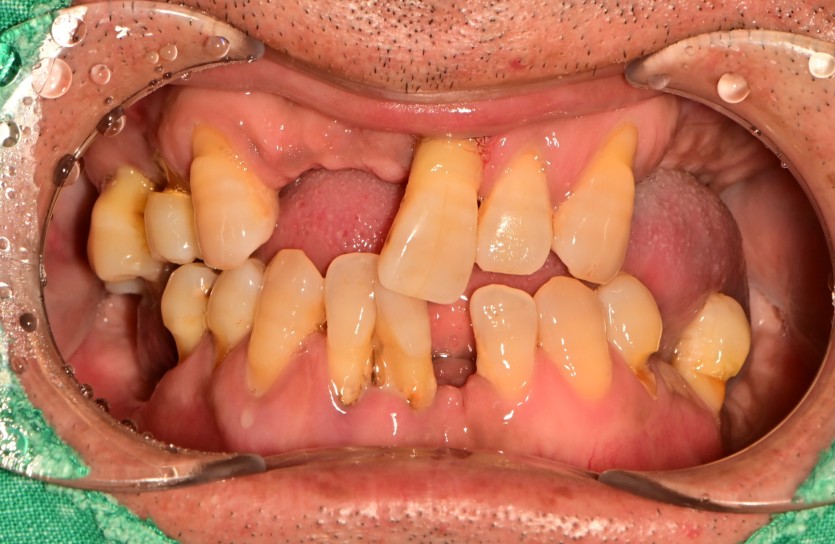

전체 임플란트 증례입니다.

18개의 임플란트로 완성하였습니다.